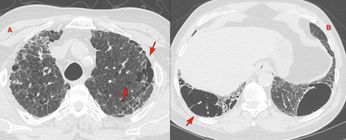

Case of the Day - 095 - 2025 09 03 - The Dots and Bands of Early Asbestosis Paid Members Public

In patients with asbestos exposure, early asbestosis presents in a distinctive manner...however these signs do not help distinguish asbestosis from other ILDs if history of exposure is not known.